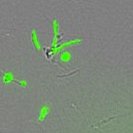

one more version of a round body with or without visualizing the GFPpic.twitter.com/zX4MbZfvUW

A bit delayed but here you go. One spirochete that has almost folded on itself in this moment next to a round body. On the left you're looking in phase, on the right you're looking also with GFP (green fluorescent protein), which these borrelia are engineered to produce.pic.twitter.com/pVFmE0OzLd